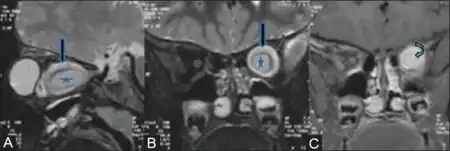

a-c)Optic nerve glioma

Optic nerve gliomas are diagnosed using magnetic resonance imaging (MRI) and CT scans.[6] The tumor adopts a fusiform appearance, appearing wider in the middle and tapered at the ends.[6] Enlargement of the optic nerve along with a downward kink in the mid-orbit is usually observed.[6] While CT scans allow for optic nerve evaluation, MRI allows for intracranial evaluation to observe if the tumor has extended to other regions such as the optic chiasm & hypothalamus.[7]